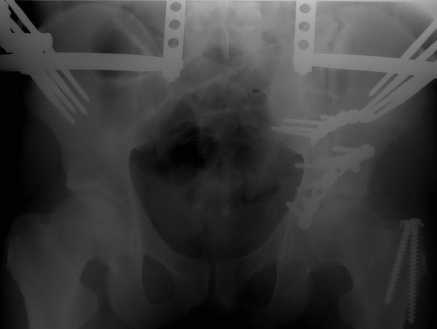

Добрый вечер уважаемые коллеги. Прошу прощение за долгое молчание( компьютер был в

долгосрочном ремонте). Больного с 9-ти месячной травмой таза мы прооперировали.

Оценив свои возможности и совместив с вашими рекомендациями и советами( большое спасибо

Рункову!), пошли задне-наружным доступом, с отсечением большого вертела. Закрепились

2-мя пластинками. Сверху закрепили аппаратом( передней рамой). На область перелома самого

гребня повздошной кости не вмешивались. Снимки высылаю. Жду ваших отзывов и комментариев.

Всем большое спасибо за активное участие в лечении больного. С ув.Андрей